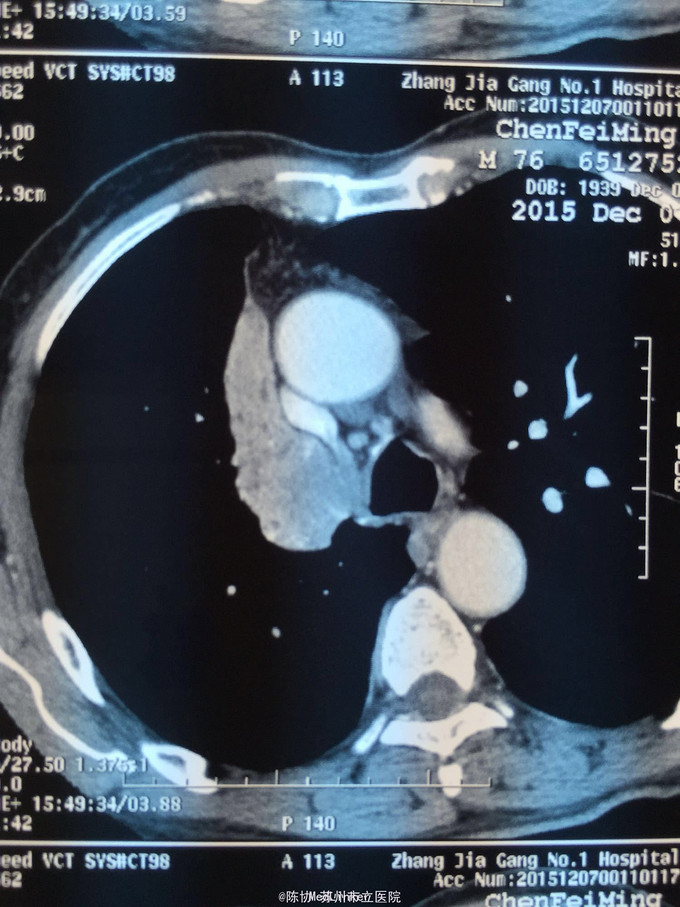

主诉:体检发现右上肺不张半月 77岁男,半月前体检发现右上肺不张,无不适。无消瘦,无咳血,无干咳。去年4月右上肺炎,抗生素治愈,当时CT未见肺肿块。入院支气管镜发现右上支气管开口组织增厚闭塞,开口近侧有隆起约3x3平方毫米,取活检5块病理示中度非典型增生。CT提示在右侧主支气管外侧有30x30平方毫米块影,压迫右上支气管开口处。三大常规和生化检查正常,肿瘤指标正常,TAP正常。

右侧中央型肺癌 重做支气管镜,精于定位找到病症组织,获得病理诊断来指导治疗。 胸外科医生不建议手术,理由是肿瘤位置靠近主支气管和气管,袖状切除不一定看干净。 请问正确的诊断,和比较合理的治疗方法是什么?求助大家思考评论